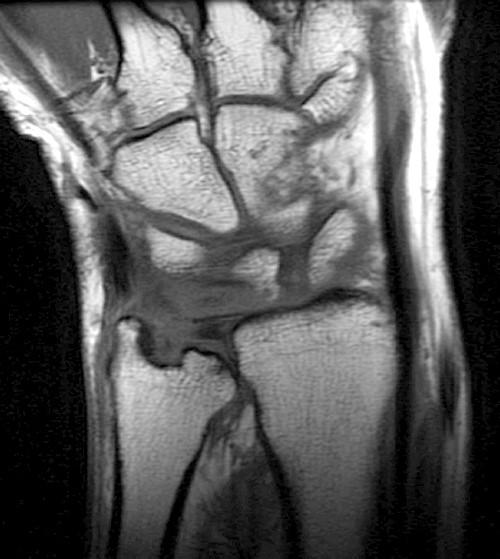

Wrist and Ankle MRI of Patients With Juvenile Idiopathic Arthritis Arthritis Ankle Mri A grading of different features of osteoarthritis can be also achieved by using the oarsi atlas 3. Ankle arthritis is a common degenerative joint disease of the tibiotalar joint that presents with pain, stiffness, and deformity of the ankle. Screen on fatsat images for bone marrow edema. We use a checklist when evaluating an mri of the ankle: Most commonly. Arthritis Ankle Mri.